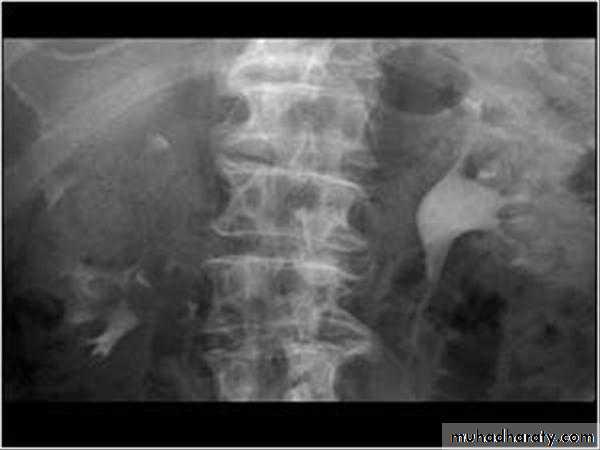

Schistosomiasis

Infestation by s.hematobium

Calcification is most important feature, mainly in bladder & lower ureters , but may involve whole ureters .

In early stage inflammation may cause cobble stone appearance.

Bladder capacity not affected.Ddgx of bladder calcification :

1. schistosomiasis .2.tumor , TB, …